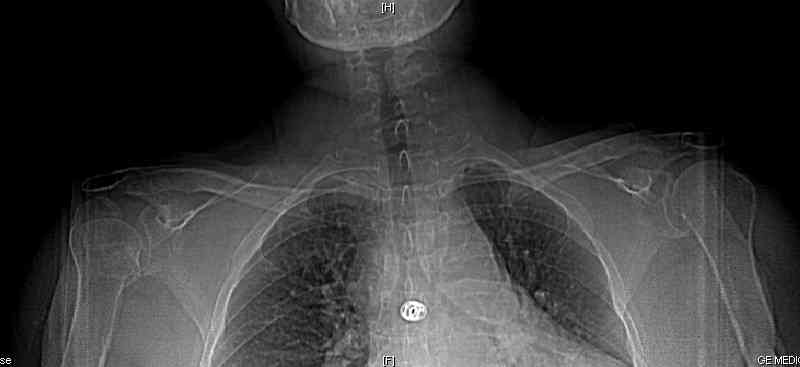

Уважаемые коллеги! Больная Н, 61 год, получила травму год назад.

Закрытый оскольчатый перелом головки правого плеча, со смещением

отломков.

Проведено консервативное лечение. Результаты представлены.

После нескольких курсов восстановительного лечения динамика

положительная, но сохраняется значительное ограничение функции

конечности, выраженный болевой синдром в т.ч. и в покое. Больная вышла

на инвалидность, не в состоянии писать, печатать на компьютере,

управляться с ложкой.